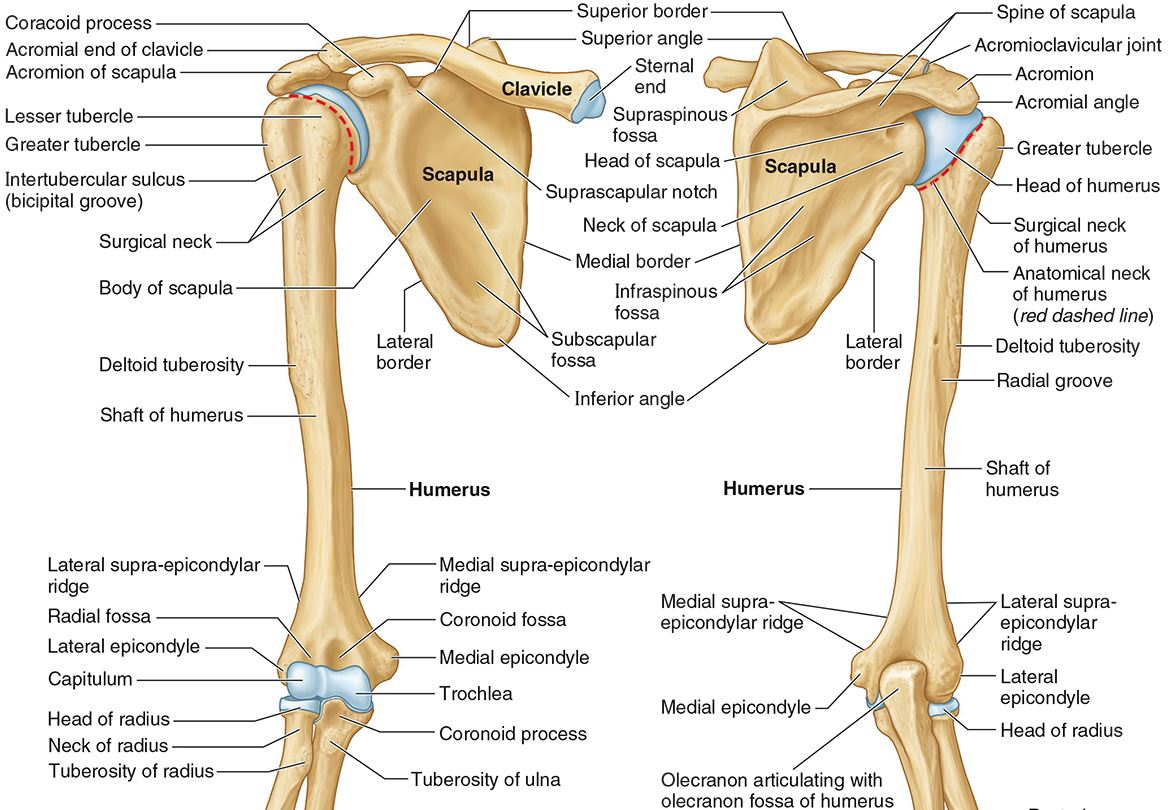

What part of the humerus is this?

The head of the humerus articulates with the scapula at the glenohumeral joint.

What part of the humerus is this?

The anatomic neck is an indentation distal to the head and provides an attachment for the fibrous joint capsule of the glenohumeral joint.

What part of the humerus is this?

The greater tubercle lies lateral and distal to the anatomic neck.

What part of the humerus is this?

The lesser tubercle lies on the anterior/medial side of the humerus, just distal the anatomic neck.

What part of the humerus is this?

The intertubercular (bicipital) groove lies between the greater and lesser tubercles.

What part of the humerus is this?

The surgical neck is a narrow area distal to the tubercles. It is a common site for proximal humerus fractures.

What part of the humerus is this?

The humeral shaft features the deltoid tuberosity laterally for the distal insertion of the deltoid muscle.

What part of the humerus is this?

The radial groove is an oblique depression that contains the radial nerve and deep brachial artery.

Which parts of the humerus is this?

The medial and lateral epicondyles are distal prominences to which many forearm tendons attach, near the elbow joint.

Which parts of the humerus is this?

The medial and lateral supracondylar ridges extend superiorly from the medial and lateral epicondyles.

Which parts of the humerus is this?

The trochlea and the capitulum (the condyles) are the most distal surfaces of the humerus, where it articulates with the forearm bones at the elbow joint

What part of the humerus is this?

The olecranon fossa is a posterior depression above the trochlea that receives that olecranon process of the ulna

What part of the humerus is this?

The coronoid fossa is an anterior depression above the trochlea that receives that coronoid process of the ulna.